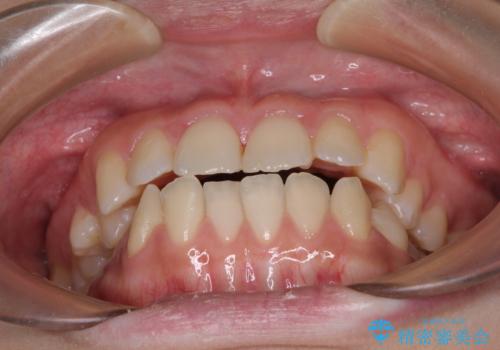

- 上下のデコボコと奥歯の咬みにくさを気にして来院された患者様です。

上顎骨の幅が下顎骨よりも小さく受け口傾向であったため、拡大装置により上顎骨の骨幅を広げて上下関係を改善し、その後インビザラインにて歯並びを整えることとしました。

下顎歯列は上顎歯列内に収まるように並んでいますが、上顎骨の幅が狭いと、下顎臼歯が全体的に舌側に傾斜した歯列となってしまいます。

舌側に傾斜した歯列は奥歯に力の負担がかかりやすく、歯磨きがしにくいなどの問題があるため、上顎骨拡大により舌側傾斜を改善することが可能となります。